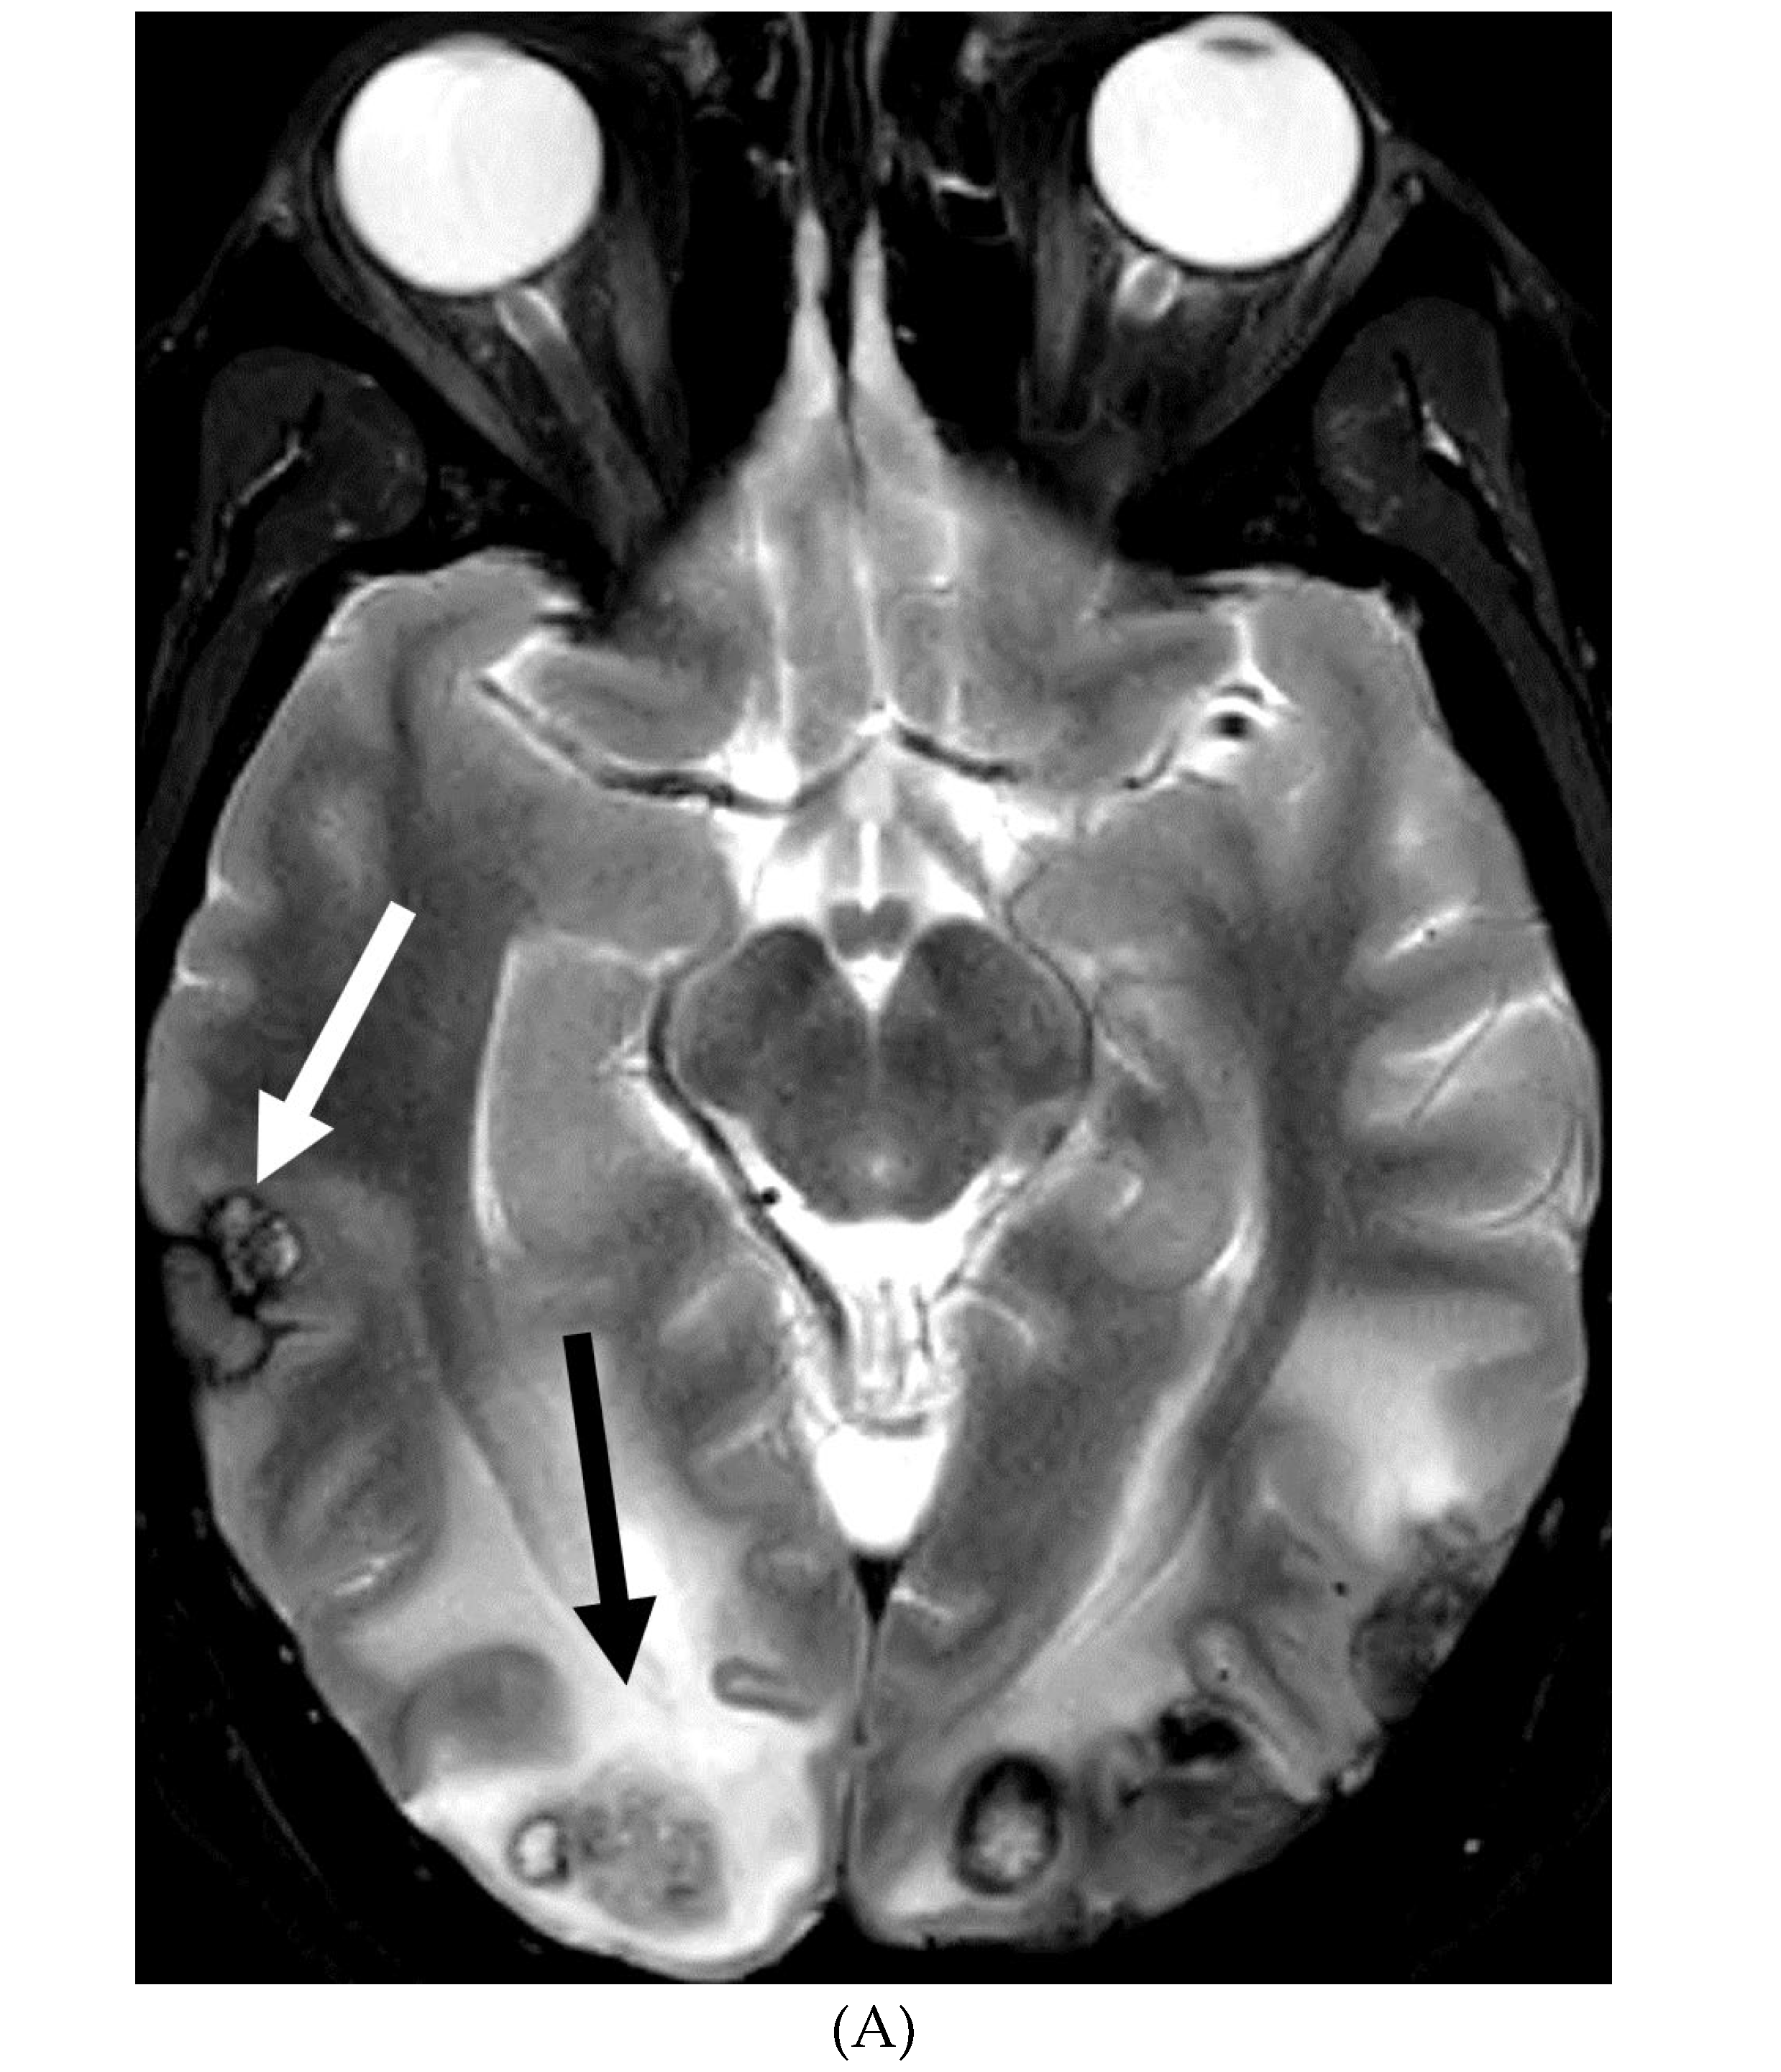

MOYA MOYA